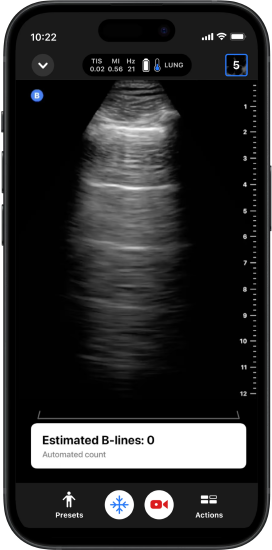

Contador automático de linhas B

Produz uma contagem de linha B a partir de apenas um clipe de ultrassom de seis segundos, simplificando a avaliação da dispneia.